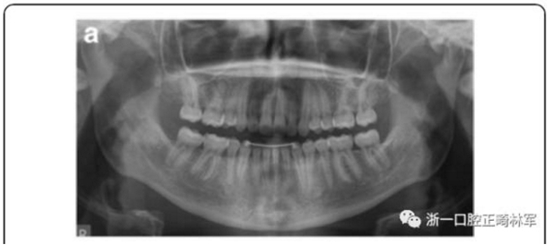

雙側(cè)I類(lèi)尖牙和磨牙關(guān)系;完全的間隙關(guān)閉(用牙線(xiàn)確定);覆合覆蓋糾正;仍有輕度的中線(xiàn)偏離。頭測(cè)分析顯示,下切牙未發(fā)生舌側(cè)移動(dòng)。